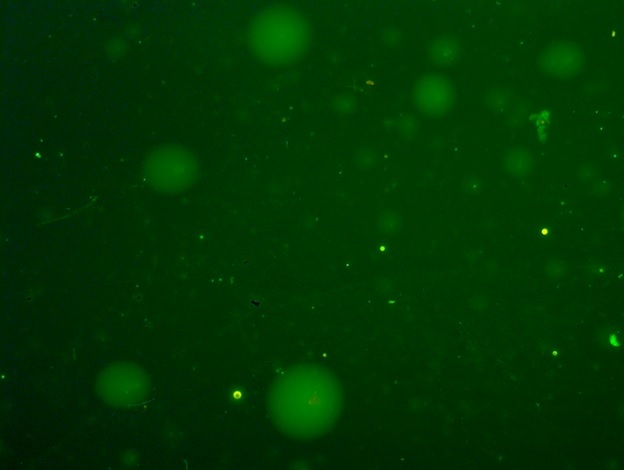

Введение. Проведена экспериментальная оценка влияния ССL4 и трансплантации клеток фетальной печени (КФП) на степень деградации и процессов репарации ДНК в клетках печени крыс, используя метод щелочного гель – электрофореза единичных клеток.

Материал и методы. Острое токсическое поражение печени крыс моделировали однократным внутрижелудочным введением крысам – самкам линии Вистар препарата CCl4 в масляном растворе в дозе 3000 мг/кг. В качестве протекционного средства использовали суспензию КФП плодов крысы 19 ДР. Для количественной оценки, степени повреждения ядерной ДНК клеток печени, применяли метод щелочного электрофореза единичных клеток (ДНК-комет) на 1, 3, 5, 7 и 16 сутки эксперимента.

Результаты. Внутривенное введение КФП через 6 часов после воздействия тетрахлорметана активировало процессы репарации ДНК в гепатоцитах крыс на 5 – 7 сутки, что приводило к снижению интенсивности повреждения ядерной ДНК. Тенденция к уменьшению числа неповрежденных гепатоцитов сохранялась и на 16 сутки эксперимента, при этом усиление репаративных процессов после введения КФП реализовалось в достоверном сокращении количества гепатоцитов с высокой интенсивностью повреждения ядерной ДНК.

Заключение. Использованный в наших экспериментах метод щелочного гель – электрофореза единичных клеток (ДНК-комет) позволил количественно оценить степень повреждения генома и его репарацию. Выявленные позитивные результаты свидетельствовали о протекторной роли КФП на структуру ДНК клеток печени крыс, после острого воздействия CCL4.